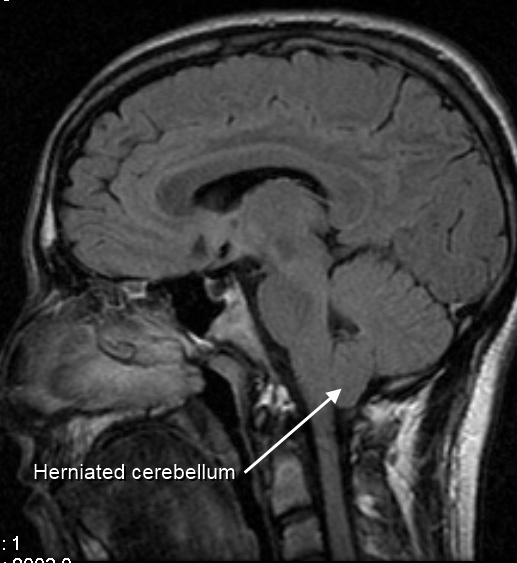

Primer serebellar ektopi olarak da adlandırılır. Serebellar tonsiller foramen magnum düzeyinden 3mm’ den daha fazla üst servikal spinal kanala herniye olmuştur. Bu aşağı kayma omurilik ile kafa içi arasındaki BOS dolaşımını tıkar. Bu sayede syringomyeli yada hidromyeli denilen omurilik içindeki sıvı birikmesine neden olabilir.

Manyetik Rezonans Görüntüleme (MRI): Tam anatomik görüntü elde etmek için önemlidir ve manyetik alan kullandığı için yan etkisi de yoktur. Beyin, beyincik, beyin sapı ve omurilik görüntülenerek Chiari I malformasyonunun tanısı ve eşlik eden ek anomalinin varlığı hakkında bilgi sahibi olunabilir.